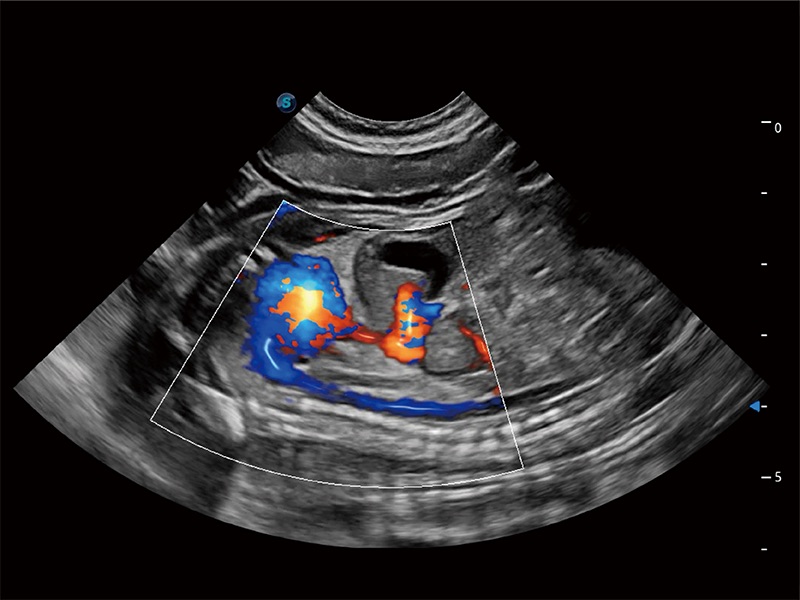

在傳統(tǒng)二維血流成像的基礎(chǔ)上,呈現(xiàn)血流的立體感,具有動感的生命力之美。即便是微小的血管也能輕松應(yīng)對,提高了血流的視覺敏感性。